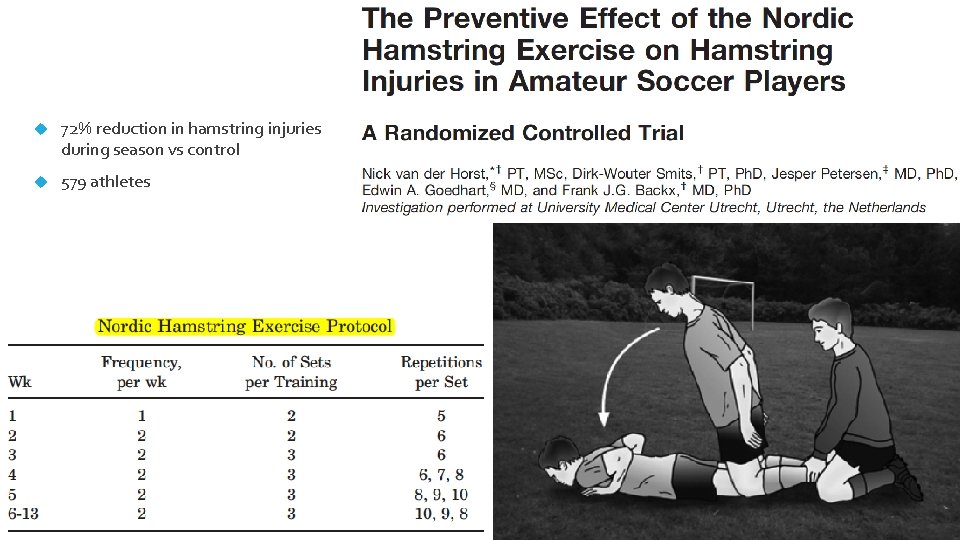

72% reduction in hamstring injuries during season vs control 579 athletes